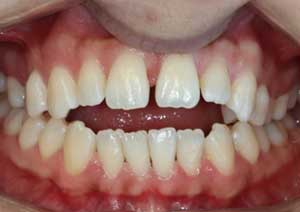

En orthodontie, une béance antérieure est une malocclusion caractérisée par l’absence de contact entre les incisives supérieures et inférieures lorsqu’on ferme les dents.

Traitement : Une ingression des molaires maxillaires avec une égression contrôlée du secteur antérieur a été réalisée à l’aide des arcs dits “Rocking Chair”, associés à des élastiques antérieurs portés de canine à canine, à droite et à gauche.

Cette mécanique permet de corriger la béance antérieure tout en conservant un contrôle précis de la position des dents antérieures et postérieures.

Après